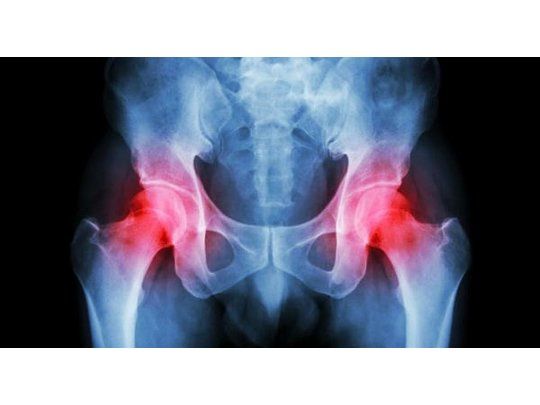

Cada día, 90 adultos mayores se fracturan la cadera